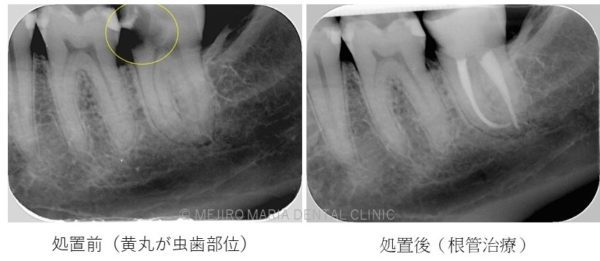

C1 ~ C2について

C2まで進行すると、甘味痛、咬合痛、冷水痛などの不快症状が確認できることがあります。

しかし、無症状で虫歯が進行する場合もあります。虫歯箇所に水や食べ物が侵入しづらい場合は知らないうちに虫歯が進行することもあるためです。

処置が必要になった場合は、コンポジットレジン修復、または歯冠修復(被せもの)で対応します。歯冠修復は一度型取りを行い、装着と調整を行わなければいけませんが、しっかりとした歯冠形態が復元されるため将来的な虫歯や歯周病のリスクを低減することができます。